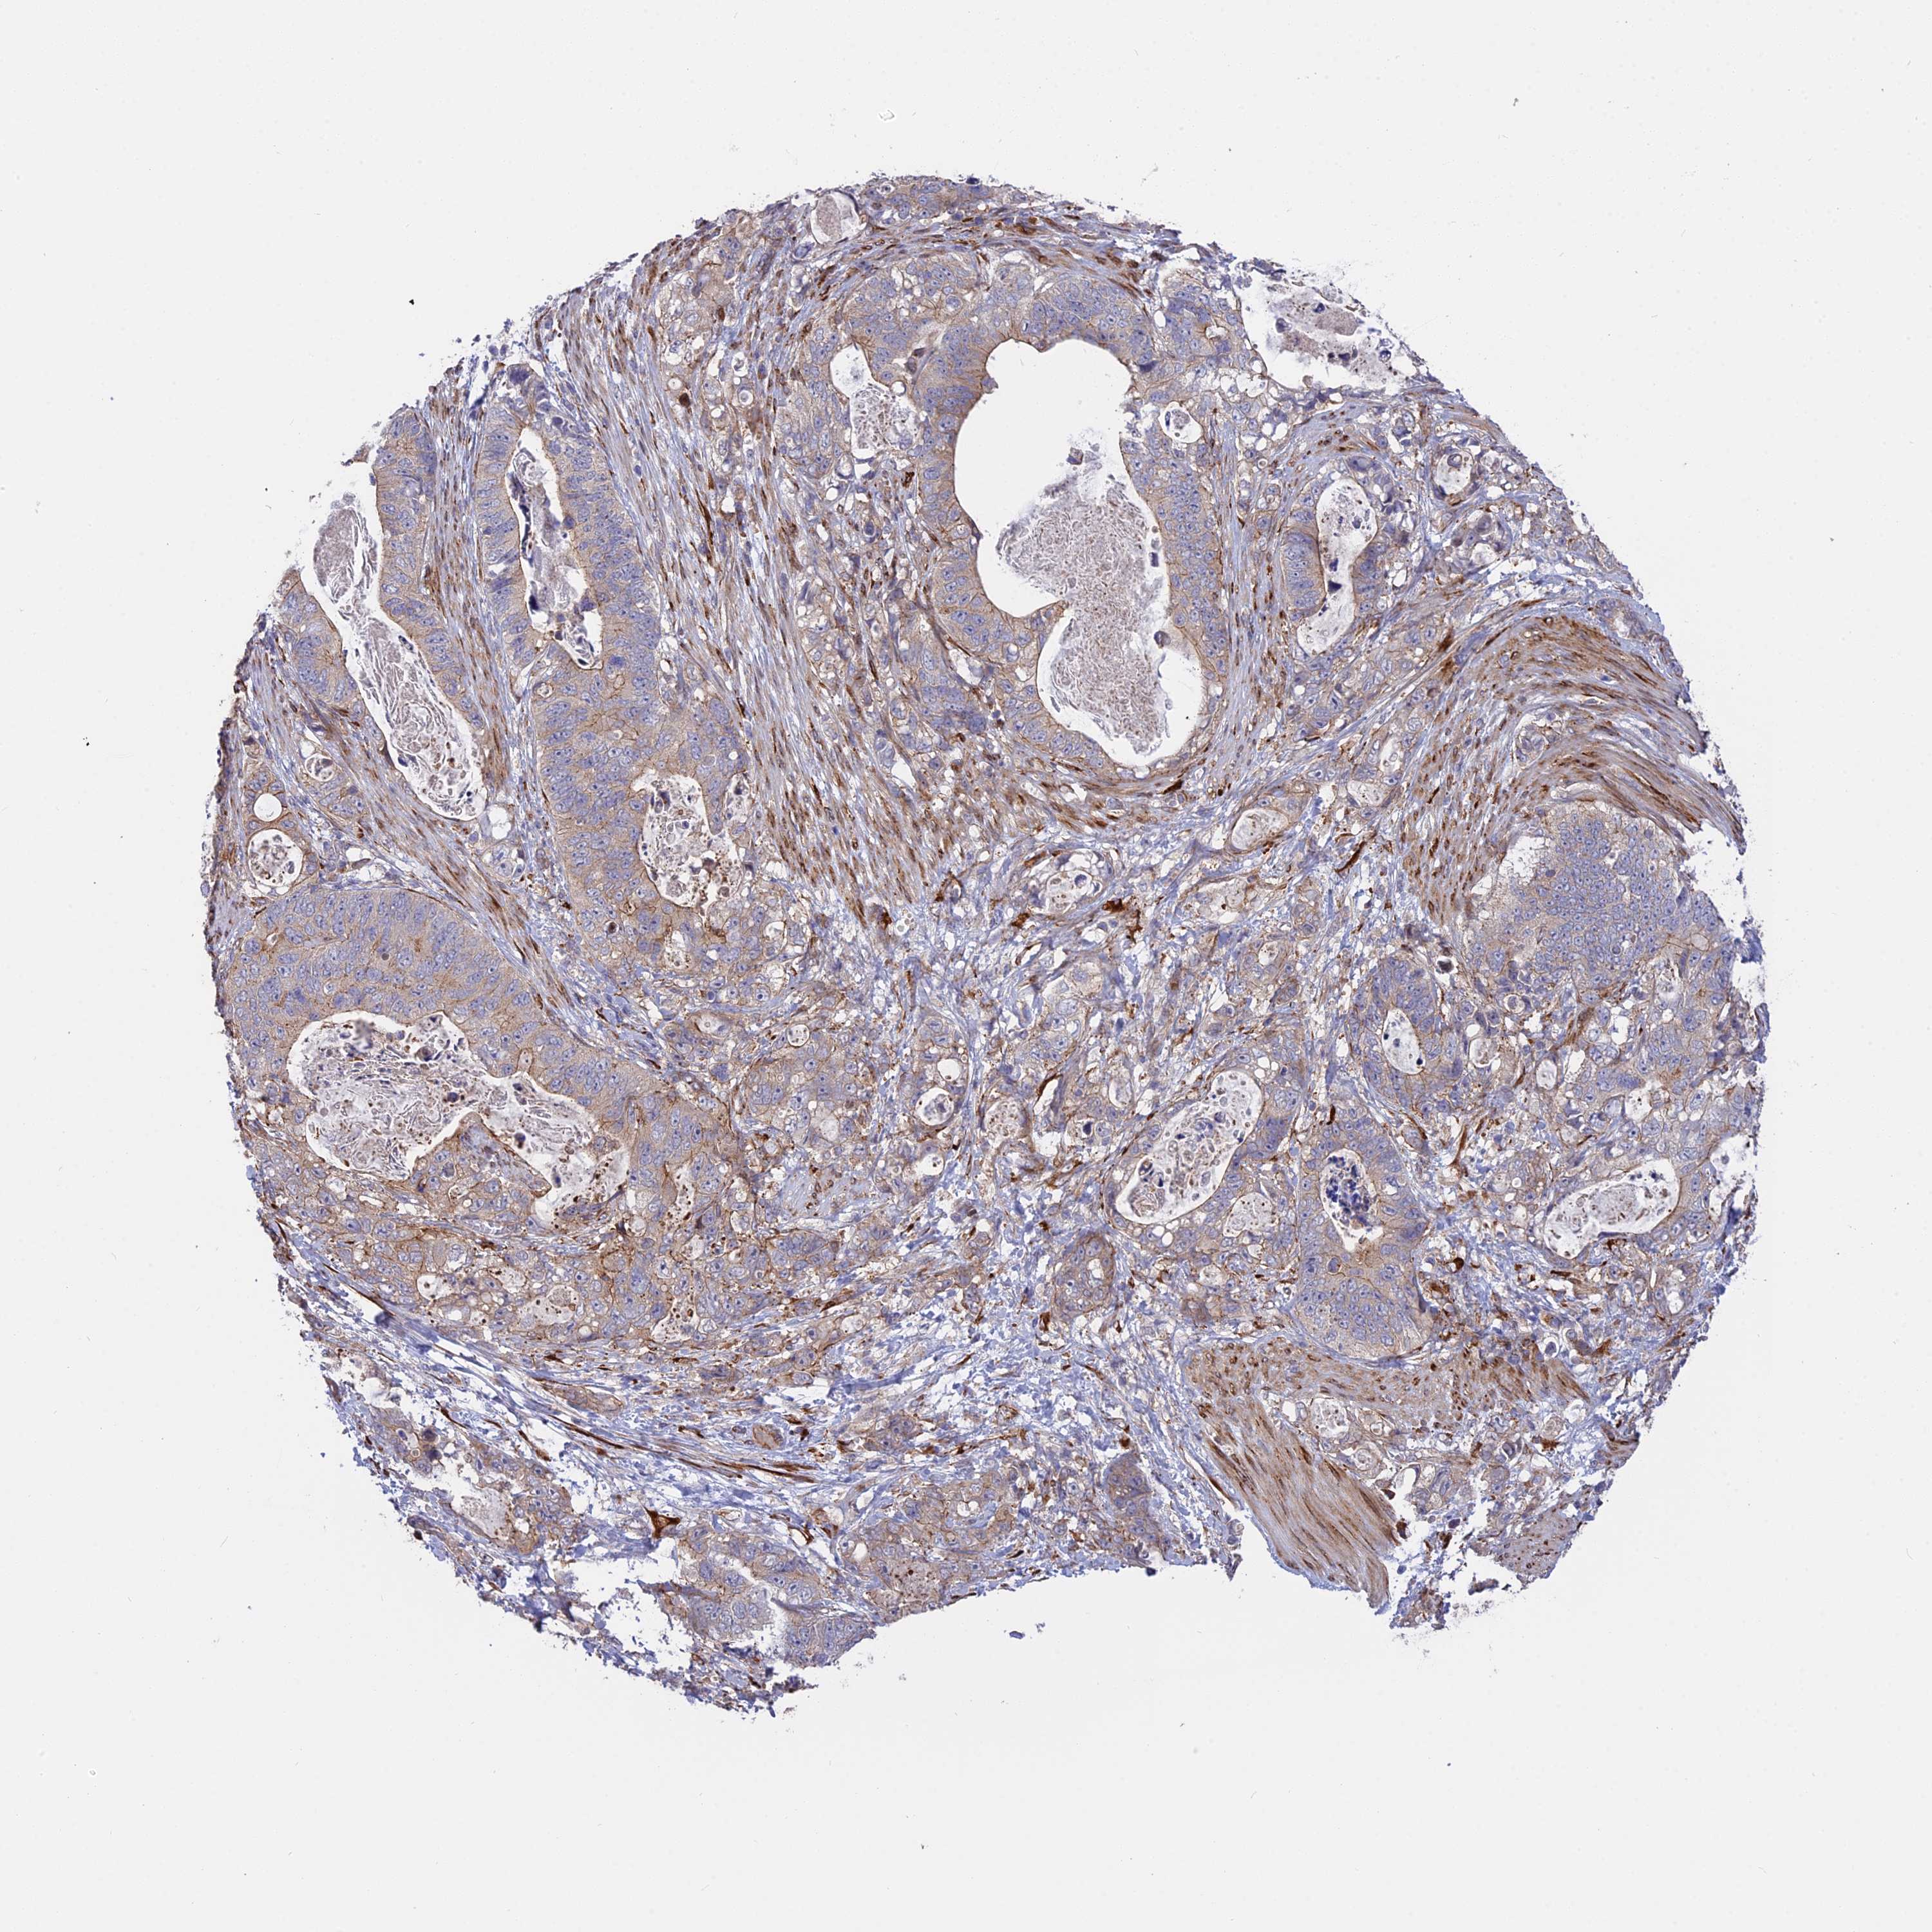

STOMACH CANCER - Protein expressioni

A mouse-over function shows sample information and annotation data. Click on an image to view it in a full screen mode. Samples can be filtered based on level of antibody staining by selecting one or several of the following categories: high, medium, low and not detected. The assay and annotation is described here.

Note that samples used for immunohistochemistry by the Human Protein Atlas do not correspond to samples in the TCGA dataset.

Antibody stainingi

Antibody staining in the annotated cell types in the current human tissue is reported as not detected, low, medium, or high, based on conventional immunohistochemistry profiling in selected tissues. This score is based on the combination of the staining intensity and fraction of stained cells.

Each image is clickable and will lead to virtual microscopy that enables deeper exploration of all samples and also displays staining intensity scores, fraction scores and subcellular localization as well as patient and tissue information for each sample.

Antibody HPA043211

Staining

High

Medium

Low

Not detected

Intensity

Strong

Moderate

Weak

Negative

Quantity

>75%

75%-25%

<25%

None

Location

Nuclear

Cytoplasmic/membranous

Cytoplasmic/membranous,nuclear

Adenocarcinoma, NOS